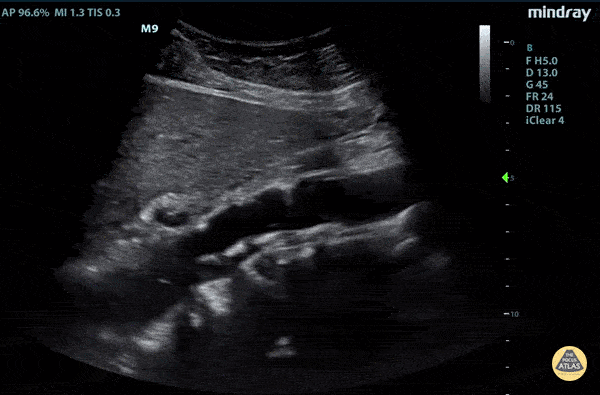

Aorta - Aortic Dissection Flap

Elderly fellow who had a headache while bike riding, with some leg weakness. No chest or back pain. Stable for hours then came to hospital, suddenly hypotension and drowsy in ER POCUS RUSH Exam performed lead to rapid diagnosis of Aortic Dissection with tamponade. A pulsating dissection flap can clearly be visualized. Claire Heslop - Pediatric Emergency Medicine - University of Toronto Hospital for Sick Children